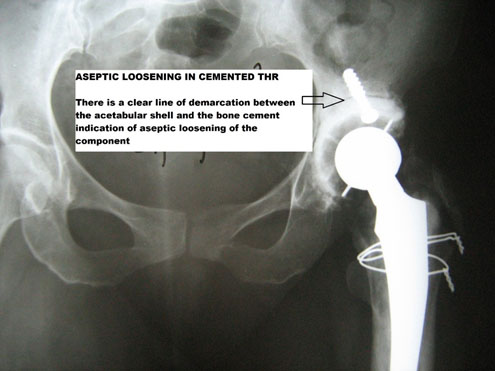

Radiology-

X rays usually demonstrate a clear line between the un-cemented cup, femoral stem, and bone, as shown in the following examples. Aseptic loosening can also be seen in cemented THR, where there will be a clear line demarcating cement bone interface.

ASEPTIC LOOSENING IN CEMENTED THR

The principle in cemented loosening is slightly different.Here, the particles generated by friction between the head of the femur and the acetabular component penetrates the area between the cemented shell and bone, leading to progressive loosening of the interface.